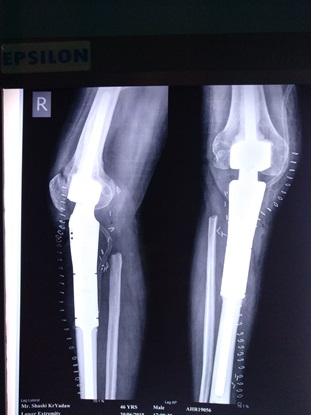

Department of Musculoskeletal Oncology

Orthopedic oncology, also known as Musculoskeletal Oncology, focuses on the diagnosis and treatment of both benign and malignant bone tumors, along with other unusual lesions affecting the musculoskeletal system. Bone cancer and soft tissue sarcomas, though rare, demand a comprehensive, multidisciplinary approach to diagnosis and treatment.